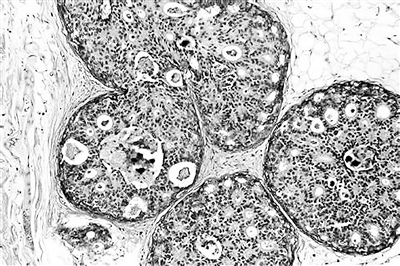

乳腺癌细胞

据最新一期《细胞》杂志报道,加美两国联合团队开展的迄今为止最大规模的乳腺癌细胞功能调查分析,发现了数十种现有药物的新用途、药物开发新靶标及新药物组合。此项研究成果也可用来开发其他癌症的候选新药及阐明癌细胞的抗药机制。